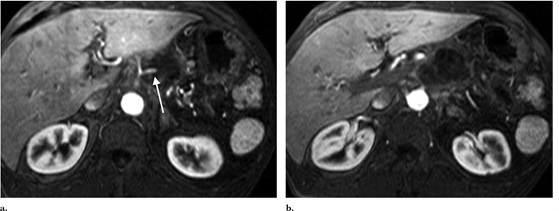

在隨后兩周的隨訪中,病人出現(xiàn)輕微間歇性疼痛,沒有出現(xiàn)疲勞,發(fā)燒或其他癥狀。每次消融后24小時(shí)之內(nèi)都使用對(duì)比增強(qiáng)磁共振成像(圖3),第二次消融后的30天預(yù)期消融區(qū)沒有出現(xiàn)增強(qiáng)。消融區(qū)的脈管系統(tǒng)尤其是脾動(dòng)脈和腸系統(tǒng)上動(dòng)脈保持明顯不變的術(shù)前外表。血清腫瘤抗原在消融手術(shù)后30天從1500U/mL減少到404U/mL90天達(dá)到407U/mL。診斷后使用PET/CT成像(圖4)如圖所示出現(xiàn)了一個(gè)輕微的氟脫氧葡萄糖周邊圈。雖然沒有觀測(cè)到參與腫瘤或節(jié)似疾病,但是在治療后的三個(gè)月PET/CT掃描出了1.5cm的肝轉(zhuǎn)移。因病變遠(yuǎn)離大血管在經(jīng)皮RF消融后肝轉(zhuǎn)移被成功治愈,然后開始吉西他濱化療。RF消融兩個(gè)月,診斷后六個(gè)月,磁共振成像顯示腹部沒有疾病惡化或復(fù)發(fā)。癌癥病源19-9水平六個(gè)月減少到236U/mL。

MR image at 1 month after IRE procedure. (a) Superior aspect of tumor shows no residual enhancement of tumor, with maintained patency and appearance of the splenic artery (arrow). (b) At the level of the superior mesenteric artery, complete necrosis is also seen.